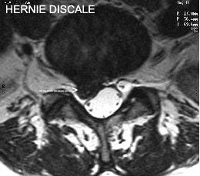

Hernie Discale

Coupe IRM